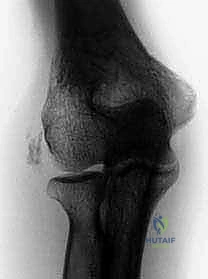

* الأشعة السينية (X-rays): لاستبعاد وجود التهاب مفاصل (خشونة) أو تكلسات عظمية.

اللقيمة الوحشية (Lateral Epicondyle) هي ذلك النتوء العظمي البارز الذي يمكنك الشعور به في الجزء الخارجي من مرفقك. هذا النتوء الصغير هو بمثابة "نقطة ارتكاز" حاسمة، حيث يلتصق بها "منشأ الوتر الباسط المشترك"، وهو عبارة عن التقاء قوي لأربعة أوتار عضلية رئيسية تتحكم في حركة الرسغ والأصابع: